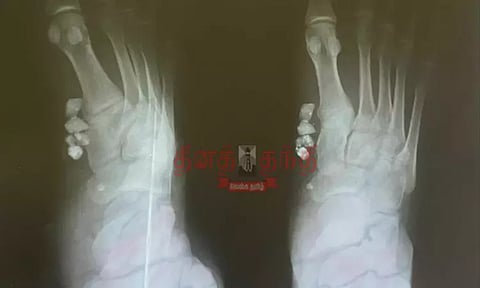

இதையடுத்து வீட்டிற்கு வந்த மதிவாணனுக்கு தொடர்ந்து காலில் வலி இந்துள்ளது. இதனையடுத்து அறந்தாங்கியில் உள்ள ஒரு தனியார் மருத்துவமனையில் சிகிச்சை பெற்று எக்ஸ்ரே எடுத்து பார்த்த போது தையல் போட்ட பகுதியின் உள்ளே 3 கல் துகள்கள் இருந்துள்ளது. மதிவாணன் விபத்தில் சிக்கியபோது தரையில் கிடந்த கற்கள் காலின் உள்ளே போயிருந்ததை அறந்தாங்கி அரசு மருத்துவமனையில் சுத்தம் செய்யாமல் தையல் போட்டுள்ளனர்.